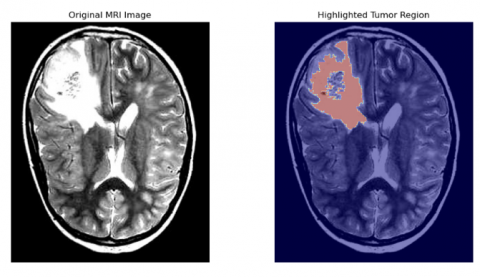

The primary objective was to highlight and segment the tumor from brain mri images. To achieve the desired results the best performing algorithm was graph-based segmentation which highlighted the tumor region accurately, resulting in perfect segmentation of brain tumor (Table 1). The dataset used to perform this project doesn’t have any ground truth labels so to evaluate the performance of the algorithm, metrics like region contrast mesaurement, compactness and circularity etc. have been used by running the algorithm on all the dataset.

Figure 11. Results of graph-based algorithm for segmentation

Figure 11 shows the successful segmentation results where the algorithm accurately highlighted the tumor region, achieving near-perfect delineation of the tumor boundaries. To further understand the limitations of the technique, Figure 12 consists of MRI images where the technique failed to highlight and segment the tumor region.